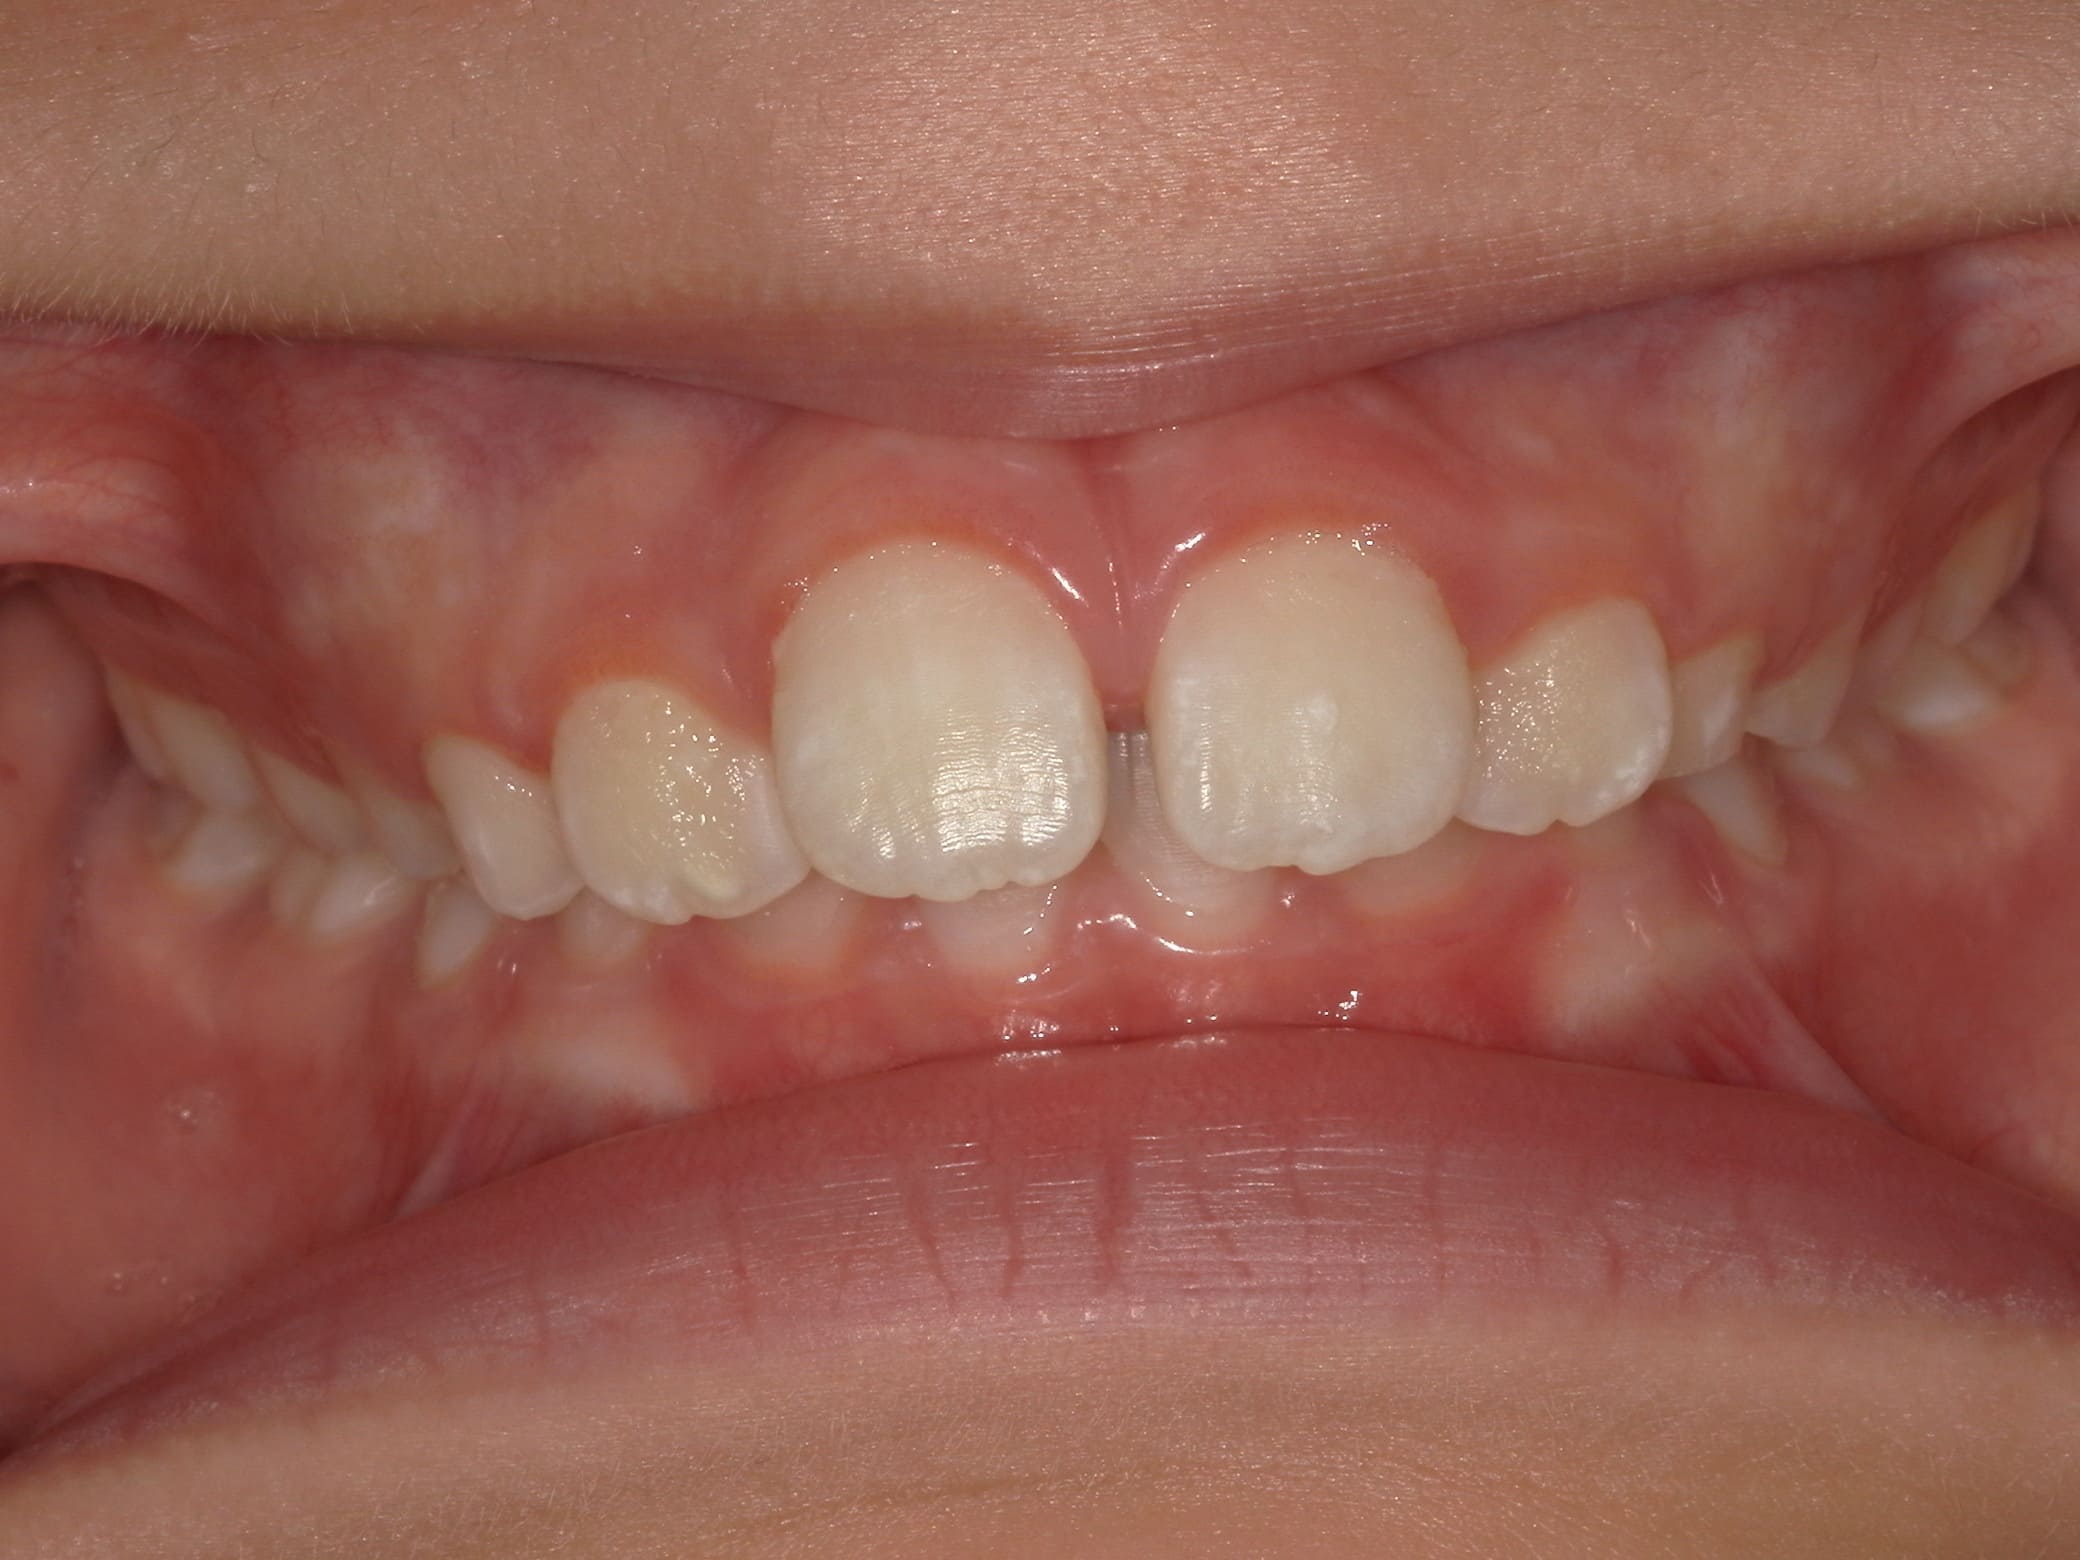

| 年齢・性別 | 男性 |

|---|---|

| 主訴 | 歯の隙間が気になる |

| 治療期間・回数 | 14ヶ月 |

| 費用 | 330,000円(税込) |